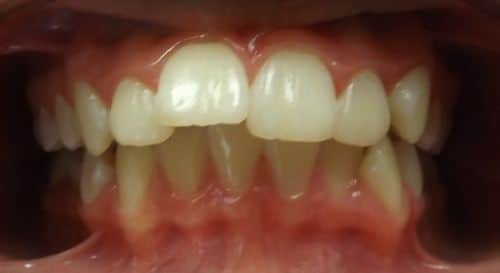

Christopher

Christopher was a Phase I case that presented with a Class III bite on the right side and a 90-degree rotation of his upper right central and lateral incisors. During Phase I we placed upper 2×4 brackets (brackets on upper 4 front permanent teeth) since Christopher still had several primary teeth left. We began Phase II and at this time Christopher had 5 mm of upper crowding and 3 mm of lower crowding. We placed brackets on the upper and lower arches and had Christopher wear elastics during treatment. Christopher ended with a really beautiful Class I bite and smile. Just look at these before and after photos.